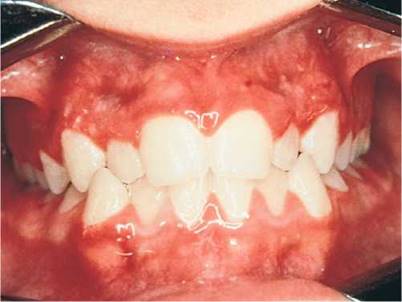

There are many causes of gingival hyperplasia, including heredity, hormonal imbalances of puberty and pregnancy, medications, and leukemia. Gingival hyperplasia is common in patients taking phenytoin (Dilantin), an antiepilepsy medication, and in those taking nifedipine, a calcium channel blocker. It has been estimated that gingival hyperplasia develops in 30% to 50% of all patients taking phenytoin. The hyperplastic gingival changes of hormonal imbalances usually recede once the hormones have returned to their normal, lower levels. Figure 12-21 depicts marked gingival hyperplasia in a patient who was taking phenytoin. Dense leukemic infiltration of the gingiva is commonly seen in acute monocytic and acute monomyelocytic leukemia. Figure 12-22 shows gingival enlargement and bleeding caused by acute monomyelocytic leukemic infiltration.

Figure 12-21 Gingival hypertrophy in a patient taking phenytoin (Dilantin).